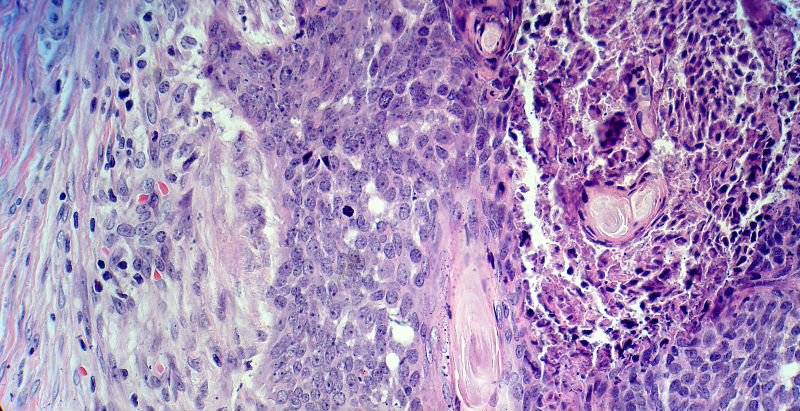

男,49岁,后枕部肿物3年,偶有破溃出血。

大体:皮肤半球形隆起,大小约2.3×2厘米,高出皮表0.8厘米,切面灰白,质地细腻。

鳞状细胞癌,基底细胞亚型

基地细胞癌。粉刺样坏死型。

基底细胞癌。

似乎既有腺样结构,也有角化珠形成,还有细胞团内的粉刺样坏死。

有坏死、囊肿、钙化及胆固醇样裂隙等结构

考虑外毛根鞘肿瘤,局部癌变。